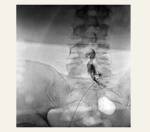

Epidurography - Discography

Test used to diagnose whether back pain is caused by a damaged spinal disc. It is the only test that can accurately tell us whether the pain originates in the intervertebral disc. The test is performed under fluoroscopy by injecting a contrast medium into the damaged intervertebral disc.